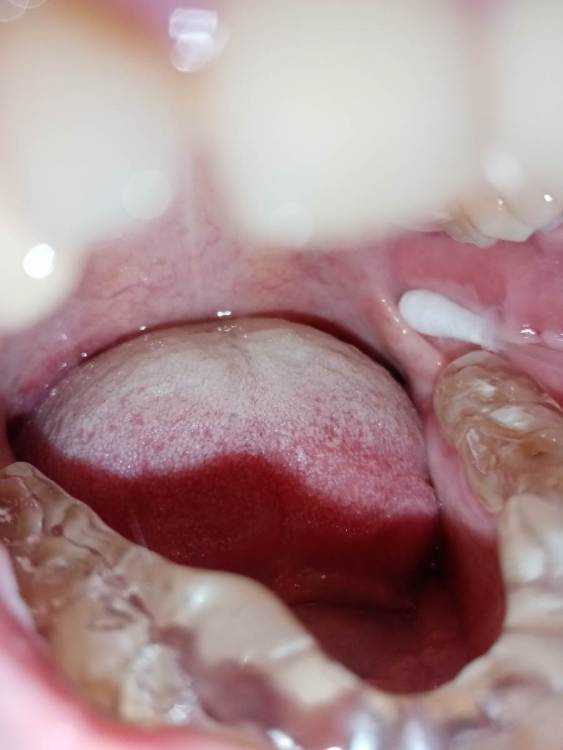

СмирноваД Опубликовано 29 июня, 2023 Поделиться Опубликовано 29 июня, 2023 Уважаемые стоматологи. Прошу Вашей помощи в поиске проблемы. Зуб удалили 2 года назад, но покоя там слизистая не дает. Болит, Разговаривать не дает вообще. Как буд-то там все пришили, и щеку и тяж со стороны горла. Какая-то шишка растет в конце верхней челюсти и как-будто давит там. Срослось оно вот таким образом "V"(со слов врача). Дергает щеку сильно , как-будто она прям пытается оторваться оттуда. и при наклоне головы прям в это место отдает. Со стороны горла тяж пришитый прям лоскутом к челюсти со стороны языка, трется об язык и тянет так сильно, что не дает разговаривать вообще, больно любые напряжения(разговаривать, глотать, пить,смеяться, и т.д.) прям чувствую как оно там все двигается, как нахождении чего-то инородного. Постоянно там все полощу, держу воду, потому что жжёт сильно. И доходит до рвотного рефлекса. Со стороны щеки,за зубом 4.7 корман. Пища попадает , и вытащить ее проблематично. Постоянно ощущение воспаления и лазию туда языком отодвигаю этот тяж, засовываю туда ватный диск, что бы просто снять напряжение и в этот момент могут быть такие жутки спазмы, что замираешь от боли. До трясучки и панических атак уже. Прикусываю там все, при чом даже с шиной (сплинт), щека лезет между зубов, приходится щеку вытаскивать.Шину ношу уже 10 месяцев, а толку нет. Рефлекторно, стараешься не двигать просто правой стороной вообще. Гнатолог , который делал шину, сказал, что нужно убирать рубцы, они все тянут. Но когда дошло дело до хирурга, хирург развел руками и сказал жить так, т.к. он ни чего сделать не может. Мало того у меня проблемы с суставом. а из-за этого напряжения на столько хуже, что к вечеру ни то что бы разговаривать, я и глотать слюну не могу. Сустав у меня теперь болит постоянно от напряжения, жуткие спазмы по всей голове, челюсти, до горла болит, с переходом на шею. При чом все врачи видят эти рубцы, что все прикусываю, трогают и мне больно, но говорят все по разному : один- надо искать, другой - там воспаление, третий- прикус, четвертый -как вы себе представляете это, это нужно было убирать сразу, пятый-сустав. Просто как идти к ортодонту с такими болями? И так же искала врача по пластике, но безрезультатно. На кт и снимках нет ни чего. Помогите, пожалуйста, хоть как-то разобраться. 230310_183333.rar Ссылка на комментарий

СмирноваД Опубликовано 11 августа, 2023 Автор Поделиться Опубликовано 11 августа, 2023 27.07.2023 в 19:43, annda сказал: Нельзя на ортодонтию идти в таком состоянии. Начните с банальной рутинной ежедневной самокоррекции хотя бы-пилатес,йога, Фельденкрайз и прочие подобные штуки. Единственные рубцы,которые у вас есть-это «линия Альба»,,следы прикусывания щек зубами.К месту удаления это не имеет никакого отношения, а к бруксизму -самое прямое. Извинете, Вы, не правы!Линия альбы! Тут ни какого отношения не имеет. Я не могу сфотографировать как выглядет вся слизистая за 4.7. зубом. Ссылка на комментарий

Bier Опубликовано 16 августа, 2023 Поделиться Опубликовано 16 августа, 2023 я вижу рубец на щеке, вы накусали его, ну если он мешает можно его отрезать. Но по источнику боли соглашусь с Анной. Ссылка на комментарий